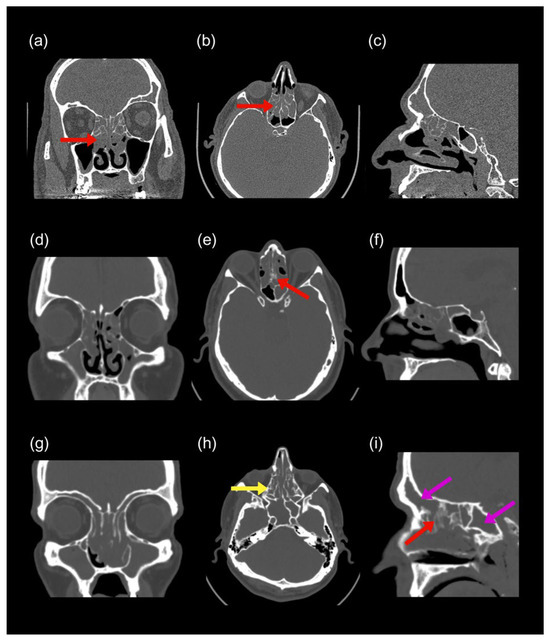

16 pages, 1722 KB

A Clinically Relevant Classification and Staging System for Chronic Rhinosinusitis with Nasal Polyposis: A Cross-Sectional Study

Diagnostics 2025, 15(24), 3197; https://doi.org/10.3390/diagnostics15243197 - 14 Dec 2025

Background/Objectives: Tissue eosinophilia plays a central role in chronic rhinosinusitis with nasal polyposis (CRSwNP), yet the spectrum of disease, particularly central compartment atopic disease (CCAD), remains underexplored. This study aimed to classify CRSwNP into three distinct phenotypes, eosinophilic CRSwNP (ECRSwNP), non-eosinophilic CRSwNP (NECRSwNP), [...] Read more.

Background/Objectives: Tissue eosinophilia plays a central role in chronic rhinosinusitis with nasal polyposis (CRSwNP), yet the spectrum of disease, particularly central compartment atopic disease (CCAD), remains underexplored. This study aimed to classify CRSwNP into three distinct phenotypes, eosinophilic CRSwNP (ECRSwNP), non-eosinophilic CRSwNP (NECRSwNP), and CCAD, based on radiologic and endoscopic features. It also proposes a novel severity-based staging system to guide clinical decision-making. Methods: A cross-sectional observational study was conducted in a single private clinic between January 2019 and August 2025. Patients were assessed using clinical history, paranasal sinus computed tomography (CT), and intranasal endoscopy. Key variables included symptom clusters, comorbidities, hematologic and atopy profiles, radiologic and endoscopic findings, histopathology, and pre-treatment SNOT-22 scores. Results: A total of 2060 patients (mean age: 29.8 ± 11 years; 51.8% male) were included. Asthma was the most frequent comorbidity (23.5%). Classification into ECRSwNP, NECRSwNP, and CCAD was achieved using integrated clinical, radiologic, and histopathologic criteria. Conclusions: This study presents a phenotype- and severity-based classification system for CRSwNP that incorporates endoscopic and radiologic features. This framework may enhance diagnostic accuracy and enable more tailored therapeutic strategies. Full article

Show Figures

Figure 1